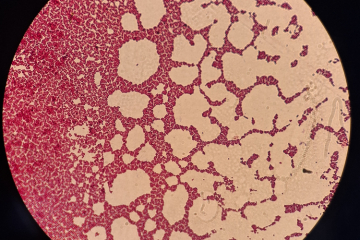

Химико-токсикологический отделОтдел по работе с заказчиком и обращению с объектами исследований (пищевые пробы)Отдел по работе с заказчиком и обращению с объектами исследований (диагностический материал)Отдел бактериологии, паразитологии и питательных средОтдел серологии и биохимииОтдел вирусологии, патоморфологии и ПЦР исследованийОтдел пищевой микробиологии и ветеринарно-санитарной экспертизыСектор обеспечения лабораторными животными